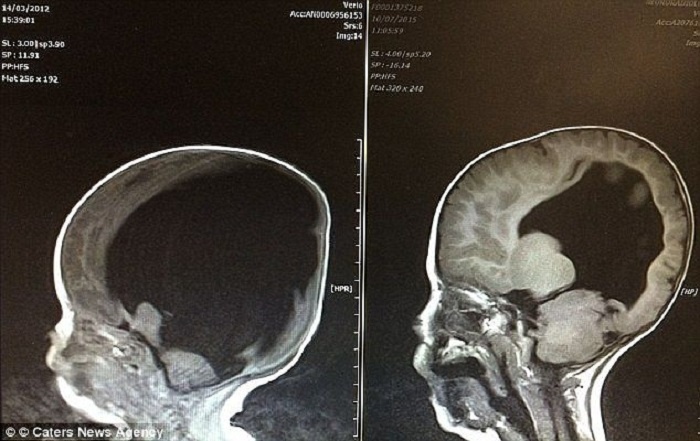

Когда Шелли и Роб Уолл из британского графства Камбрия услышали вердикт врачей, мир вокруг них должен был рухнуть. На снимке УЗИ вместо развивающегося мозга их будущего сына зияла пустота, заполненная жидкостью. Медики были суровы и единодушны: у ребенка функционирует лишь два процента мозга, он не выживет после рождения, а если и случится «невозможное», он навсегда останется «овощем», неспособным ни чувствовать, ни осознавать реальность.

Первым шагом к спасению стала сложнейшая операция. Нейрохирурги установили в голову малыша шунт — специальную трубку для отвода лишней жидкости. И тут произошло то, что наука до сих пор называет медицинской загадкой. Мозг Ноя не был «отсутствующим» в буквальном смысле — ткани были экстремально сдавлены скопившейся жидкостью.

Как только давление спало, серое вещество начало буквально расправляться и расти, словно цветок, получивший долгожданную воду. К трем годам объем мозга Ноя достиг невероятных восьмидесяти процентов от нормы. Мальчик, которому прочили растительное существование, заговорил.